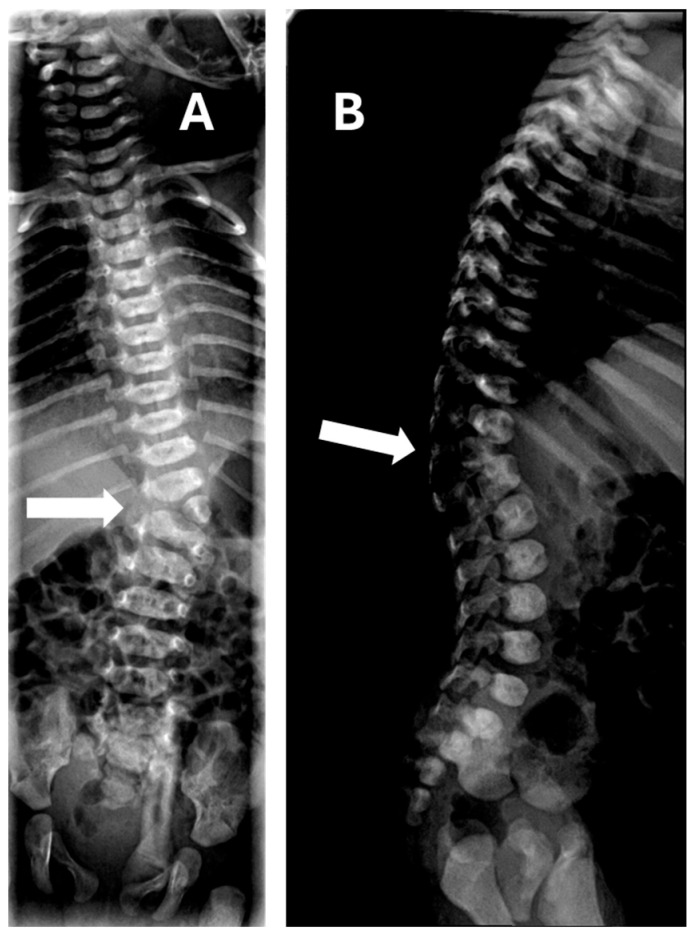

Results: Most cases were diagnosed during the second-trimester ultrasound, with the lumbar region being the most frequently affected site (60%). Multiple hemivertebrae were detected in 4 of 10 cases. One case of Marfan syndrome and two cases of VACTERL association (vertebral defects, anal atresia, tracheoesophageal fistula, renal dysplasia, and limb abnormalities) were documented. Six cases presented with additional malformations. Cases involving multiple hemivertebrae (40%) were more likely to be associated with other anomalies and poorer prognoses, while isolated single hemivertebra showed favorable outcomes, with normal development during childhood. Vaginal delivery occurred in six cases, while cesarean sections were performed for standard obstetric indications unrelated to the hemivertebra diagnosis.